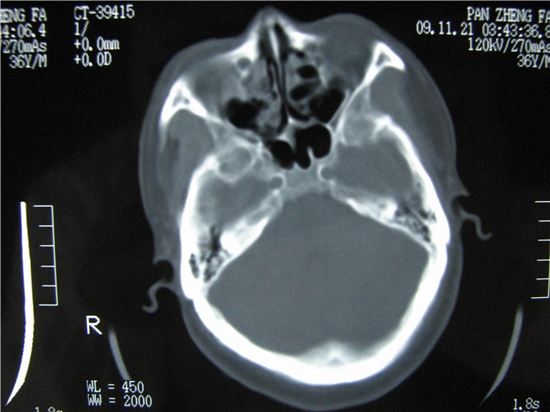

标题: CT23231:男 32岁 车祸伤,鼻腔内出血明显。 [打印本页]

标题: CT23231:男 32岁 车祸伤,鼻腔内出血明显。

额窦里是什么,骨窗怎么不清晰,是不窗宽窗位的事。

不排除鼻骨骨折!

不排除鼻骨骨折!额窦骨瘤?

额窦内及额部软组织内可见多发游离类骨质密度影,考虑额骨骨折可能。

鼻骨层面较少,无法判断鼻骨。

建议薄扫一下。

额窦致密骨瘤,前额部及右顶部头皮损伤伴异物存留

左侧额骨、鼻骨骨折,头面部软组织肿胀。

左侧额骨、鼻骨骨折,额窦内的应该是游离骨块